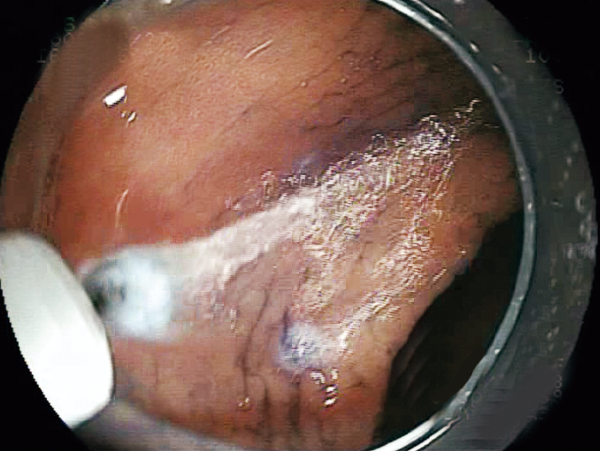

Able to incise the target tissue smoothly from side to side and up to down.